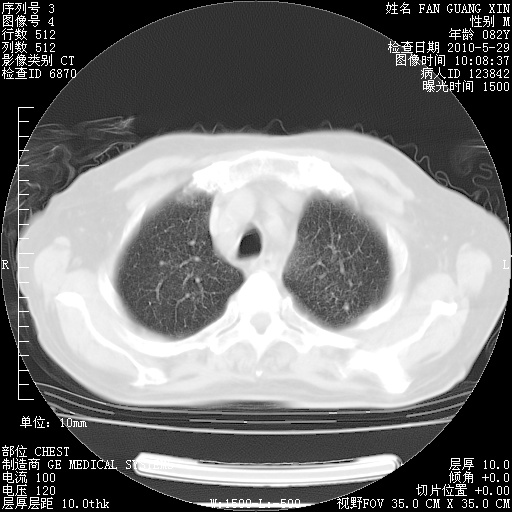

还需要哪些辅助检查?我们医院排除真菌感染没有任何检验方法,胸片好像能够排除肺部真菌感染。